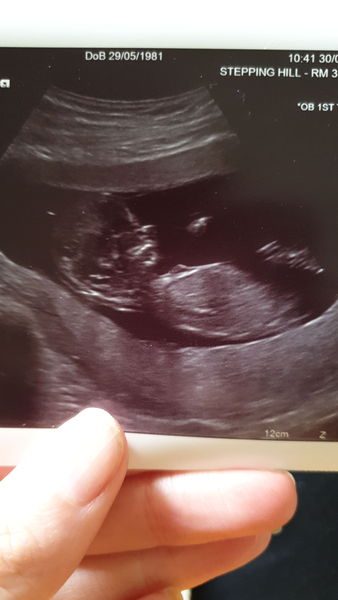

Such lovely scan photos @littledinosaurs @elb1504 - congratulations xx

@nicoletia beautiful scan, congrats! I need to have a read up on Nub theory, as well. Clueless about it right now!

My scan was quite late in the afternoon and i had to leave and return three times because baby would not behave. Did everything it shouldn't, faced the wand, back to the sonographer or curling up in a ball on its side. Clearly stubborn like mum. I had to go for walks, shake pelvis around and eat a sugary snack before we finally got the right angle for the tests. OH found it all highly amusing.

Saw a good heartbeat and lots of arm waving action, and was nice to see baba for longer due to multiple trips.

I've been put forward a few days, measured at 13+3 with new EDD of 3rd April.

Congratulations Bristol :) beautiful photo xx

All went ok with my scan. Put me forward a few days so revised expected due date of 9 April 2020.

Congrats @BristolBear and @Dumbo1981 – lovely pics! Glad I wasn't the only one with a stubborn baby! Smile

@BristolBear @Dumbo1981 congrats ladies, lovely scan photos!

The second half of the appointment was much more positive and the midwives and Drs were lovely. They did confirm the measurements for me as the Sonographer was able to provide it. I am only measuring 11+4 and I wish I'd have gone a week later - just really want to get through this first 13 weeks. My midwife said if I was really worried about MC etc then 16 weeks is the week I'm aiming for to feel like I'm in the clear. My scan isn't that great, but have attached it in case anyone wants to see. X

April 2020 Babies - Thread 2!